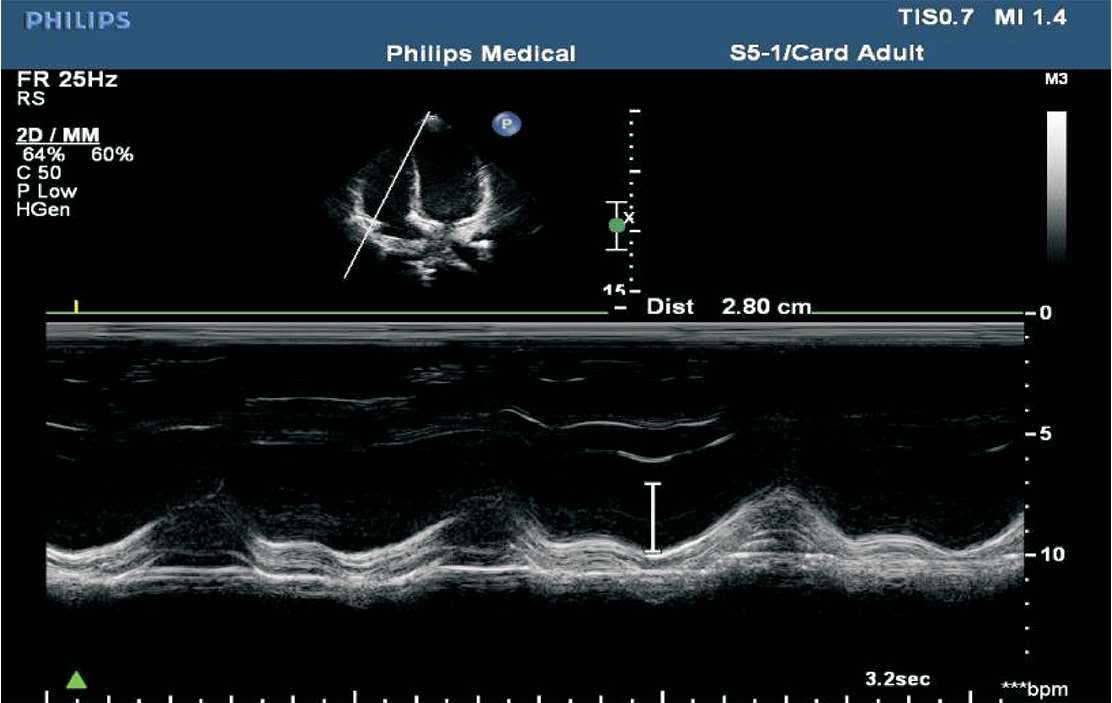

(1)三尖瓣环收缩期位移(TAPSE)。用M型超声测得三尖瓣外侧瓣环的运动曲线,在曲线上测量舒张末期最低点至收缩末期最高点之间的距离,正常时≥16 mm,<16 mm时考虑为右心室收缩功能降低(见图1-41)。

图1-41 三尖瓣环收缩期位移